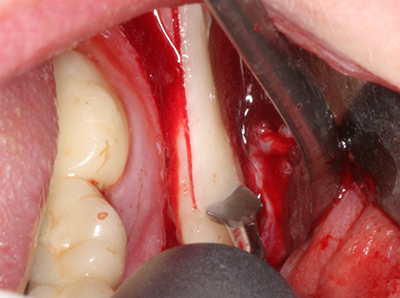

Indication: Preparation near nerves

When surgical procedures are performed on bone in the immediate vicinity of sensitive structures such as blood vessels or nerves, rotary instruments pose a significant risk of iatrogenic injury. Piezoelectric devices can be helpful for preparation of bone covers and removal of hard tissue close to nerves, particularly for exposure of nerves after iatrogenic injury but also during nerve lateralization for resective and reconstructive procedures or implant placement (Fig. 17-20). Light contact between the piezotip and the nerve does not generally result in damage but proceeding incautiously with saw-like motions or attachments where a residual bone substrate remains may cause temporary or even permanent nerve damage. However, the risk of damage is considered to be substantially lower than when using saws or milling instruments (Pereira, Gealh et al. 2014).